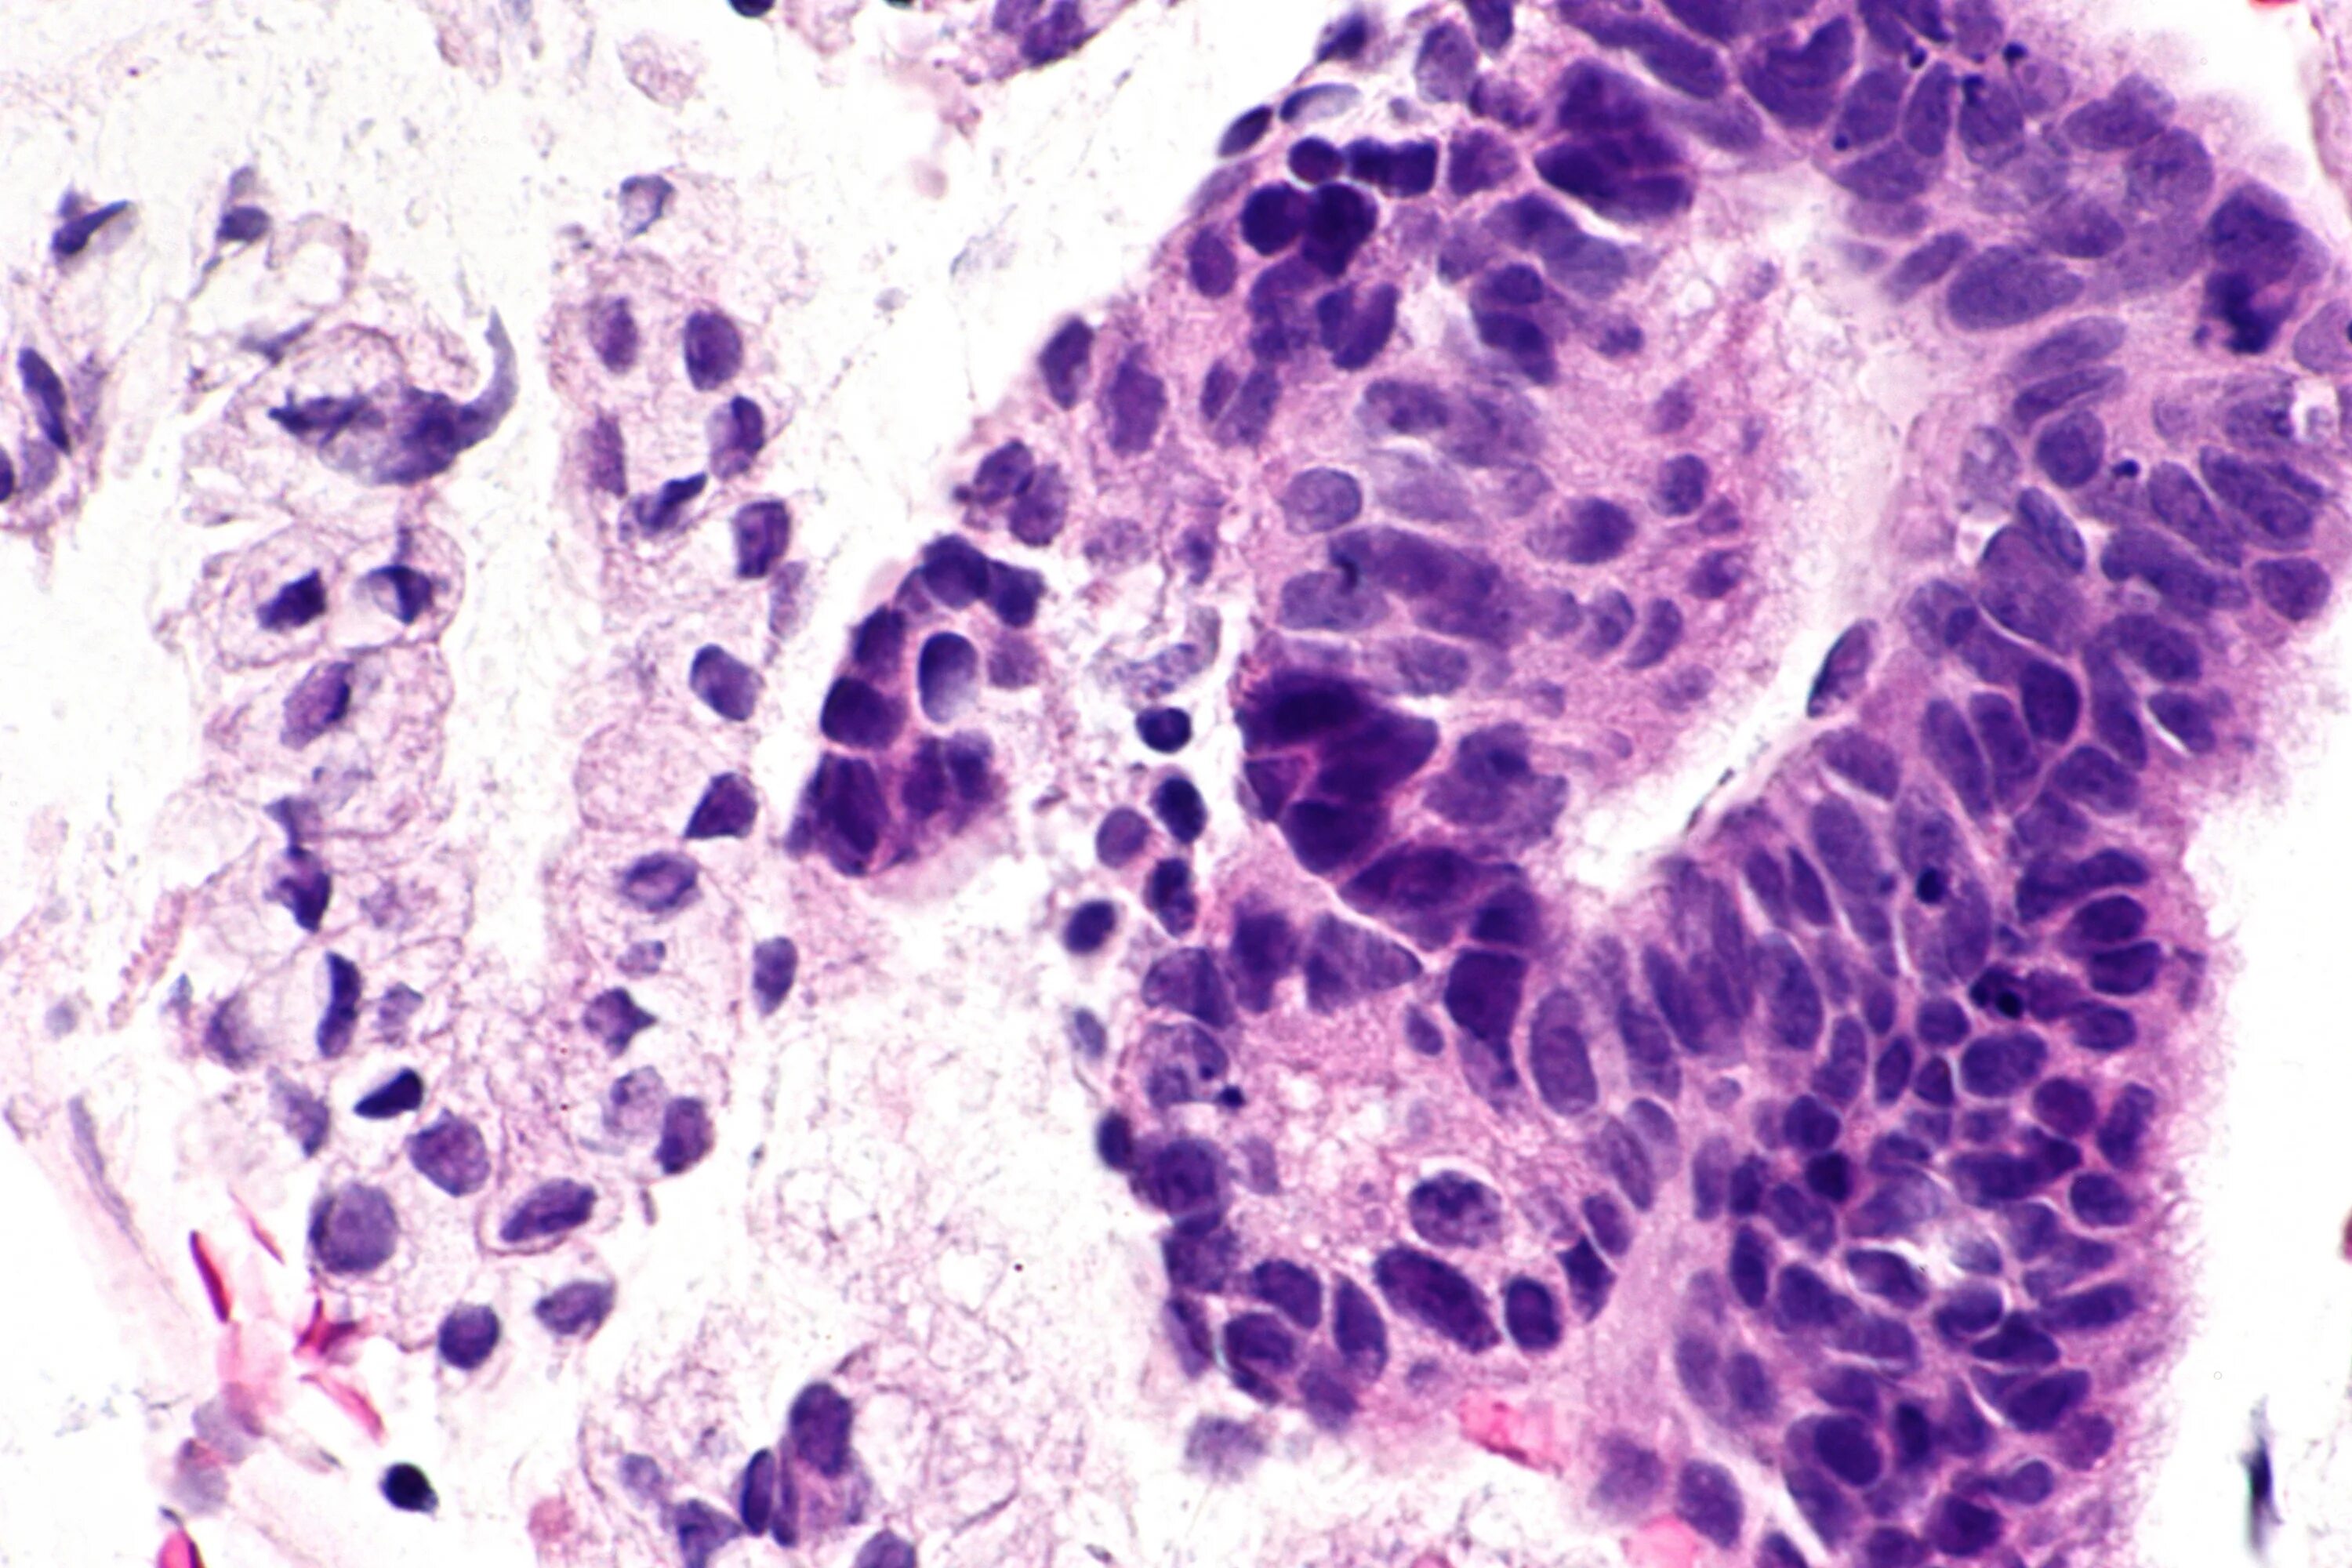

Гистологически аденокарцинома